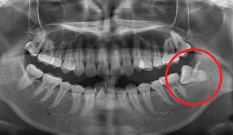

자료 채득

X-ray, 구강 내ㆍ외 카메라 사진, 치아 모형, 턱관절 및 치주 상태,